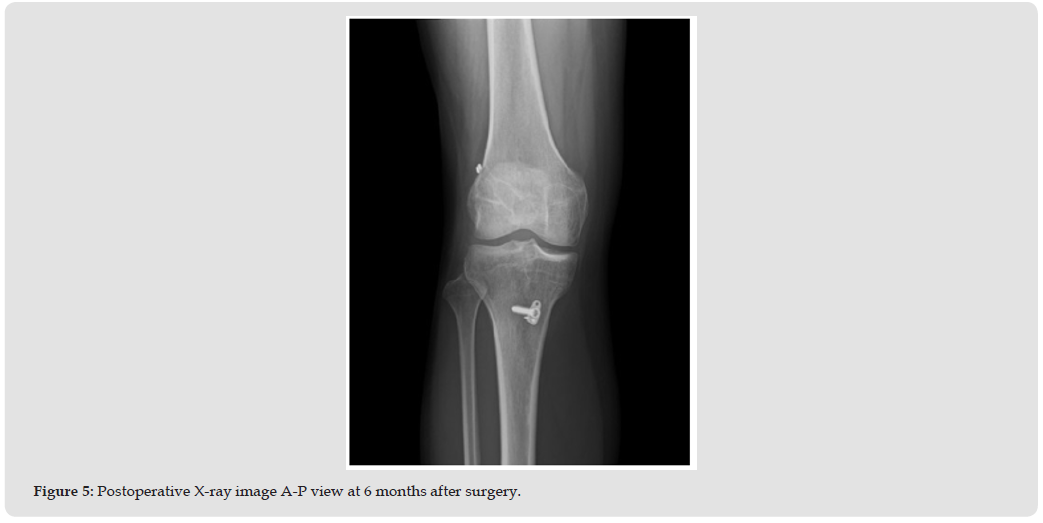

Due to persistent severe right knee pain and gait disturbance, a knee brace was applied, and conservative treatment, including muscle exercises, was initiated. One month later, follow-up MRI showed that the bone bruise had almost completely resolved (Figure 4), and her pain had gradually subsided; however she continued to experience episodes of knee instability. Arthroscopic examination revealed a slightly lax ACL and no meniscal tear. ACL augmentation was performed using a 7 mm single-bundle semitendinosus tendon graft (Figure 5). Postoperatively, a knee brace was worn on the right leg for 2 weeks, and range-motion exercises were allowed. Full weight bearing was allowed at 5 weeks. Six months after the surgery, the patient was largely aymptomatic and had resumed daily activities. Her Lysholm knee score was 82.

In this case, the bone bruise was likely due to stress-induced disruption of the subcortical trabeculae rather than a direct traumatic impact. It is therefore considered that a partial ACL injury was sustained, and continued activity under this condition transmitted repetitive stress from anterior knee instability to the tibial bone marrow, potentially leading to the development of the bone bruise. Kroker et al. reported that 19 of 21 bone bruises healed within 2 months and all 21 resolved by 8 months. However, subchondral bone loss persisted up to 10 months [14-16]. In this case, the bone bruise had almost healed by approximately 2 months, likely due to the use of a knee brace and the consequent reduction in stress related to anterior knee instability. Regarding the relationship between pain and bone bruising, Driban, et al. [17] reported that increased bone bruise volume is associated with lower Knee Injury and Osteoarthritis Outcome Scores in the absence of depression fractures [17]. Similarly, in this case, the bone bruise almost disappeared in parallel with the reduction of pain symptom.